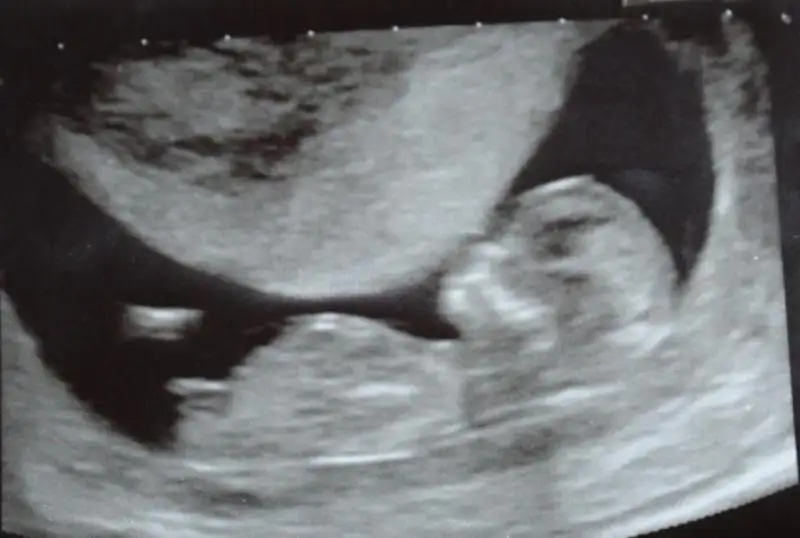

Buda benim bebisimn rsmi szce ne? Ben anlamiorm nub dan

evt bu resim icin erkek dedim cnm bnmm yukari bakio nub ucu

Canım bak bu orkıde hanımın koydugu foto yukardakı kız bebek ve benım foto aynı ona benzıyor ama : ) kırmızı gıbı olanlar benım fotom dıgerlerı orkıde hanımın kız bebek dıye koydugu fotolar bı bakabılırmısın..ayrıca arkadaslar anlayanlar benım fotomada yorum yapıverın rıca edıyorum lutfen lutfen lutfen :)

En sondakı foto da orkıde hanımın koydugu erkek fotosu nubu nasıl yukarda benımkı paralel gelıyo gıbı